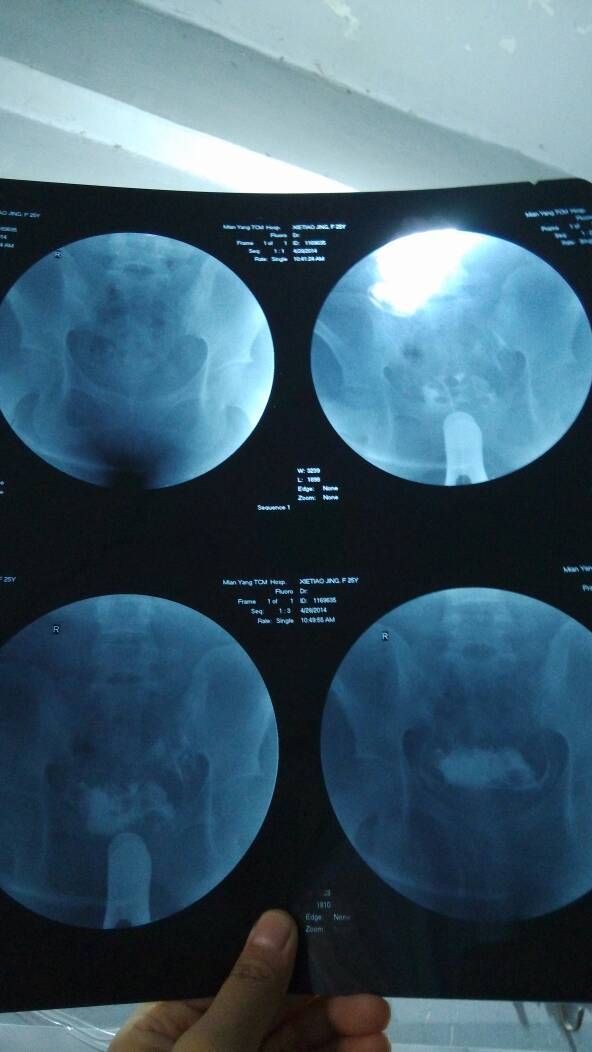

我的输卵管有堵的很厉害吗,保守治疗能好么 我的输卵管有堵的很厉害吗,保守治疗能好么 点击展开 Dora 2014-08-19 17:08 为您推荐: 其他回答 你好,一般这个时候像你这样的情况你最好都是建议能够及时的做手术,否则的话基本上什么打针吃药没有作用。 adfaffq 2014-08-19 21:37 相关问题 宫外孕保守治疗后有没有可能输卵管是不 堵的? 输卵管妊娠保守治疗期间的护理措施有哪些